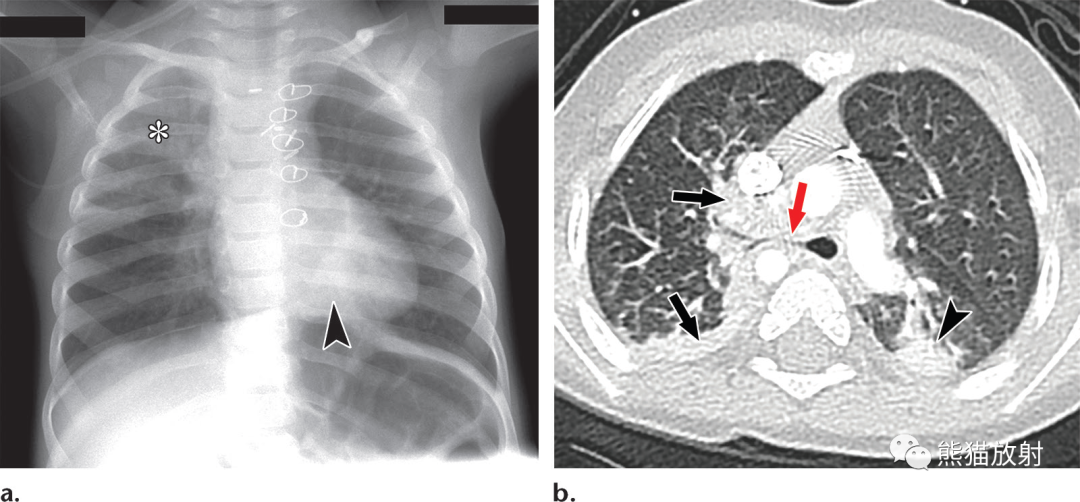

图片

1 6个月大的男孩,法洛四联症,复发性肺炎。右气管支气管移位。(a)仰卧位胸片显示右上叶(*)实变,左下肺心后区域(箭头)部分实变。(b)3天后增强胸部CT显示右肺上叶(黑箭)和左肺下叶(箭头)部分实变。红色箭头=移位的右气管支气管通向实变的肺实质。